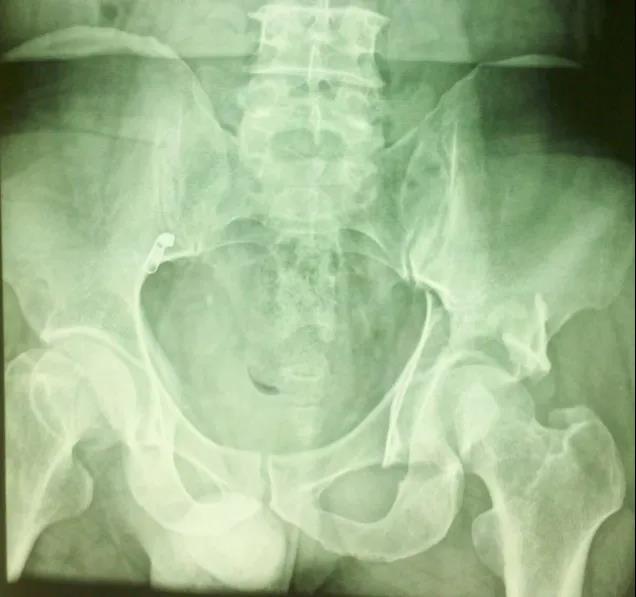

闭孔斜位片:(重点观察前柱、后壁)

髂骨斜位片:(重点观察后柱、前壁)

——典型案例——

微创插板病历后路有限切开,结合前路微创插板内